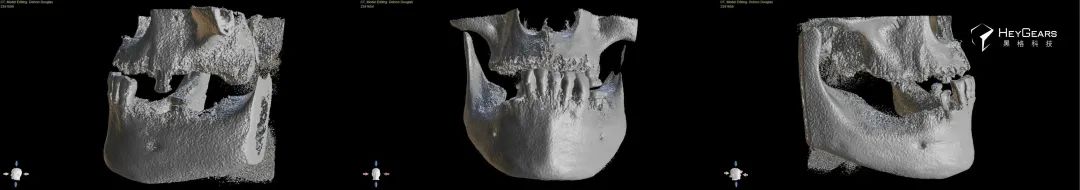

1685696033459.jpg)

▲术前3D扫描图像